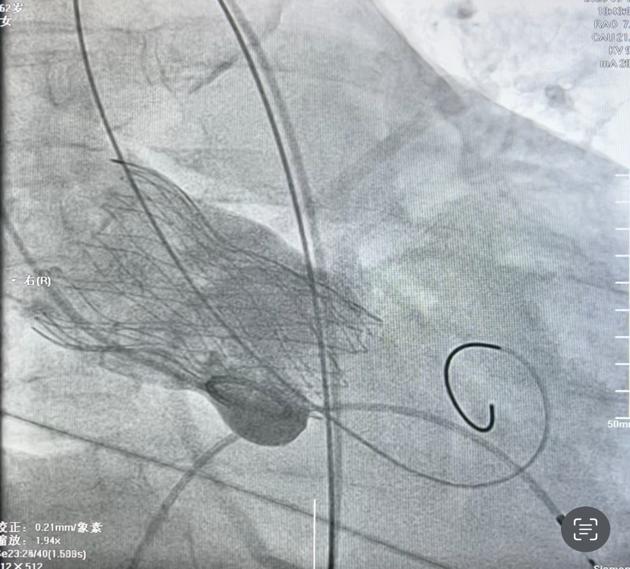

患者之一为63岁女性,胸闷胸痛不适,近段时间反复出现胸闷胸痛不适,来院就诊检查为“冠心病、心绞痛、高血压病3级、2型糖尿病”收治入院。心脏超声提示左房增大,室间隔增厚,升主动脉略增宽,瓣膜重度反流。术前冠脉造影未见明显异常。主动脉瓣重度返流患者药物治疗效果不明显,需手术干预。术前CTA评估梁有峰主任及我院多学科充分术前讨论,制定了详细手术方案。在梁有峰主任指导下,心血管内科一病区医疗团队成功为该患者植入 TaurusElite AV29瓣膜,术后超声结果显示瓣膜工作正常,血流动力学良好,术后第二天ICU病房转入普通病房。

病例1:重度主动脉瓣关闭不全瓣膜植入      病例2:重度主动脉瓣狭窄瓣膜植入